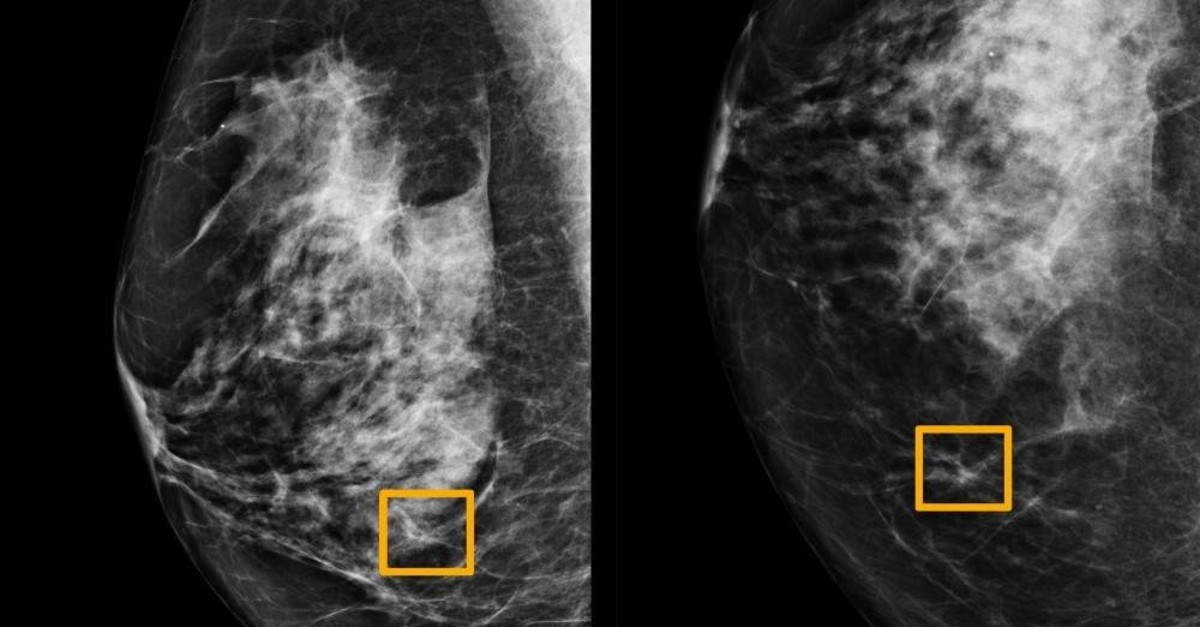

A yellow box indicates where an artificial intelligence (AI) system found cancer hiding inside breast tissue, in an undated photo released by Northwestern University in Chicago, Jan. 1, 2020. (Northwestern University via Reuters)

An artificial intelligence system proved as good as expert radiologists at detecting which women had breast cancer based on screening mammograms and showed promise at reducing errors, researchers in the United States and Britain reported.

The study, published in the journal Nature on Wednesday, is the latest to show that artificial intelligence (AI) has the potential to improve the accuracy of screening for breast cancer, which affects one in eight women globally.

The study showed the AI system could identify cancers with a similar degree of accuracy to expert radiologists, while reducing the number of false positive results by 5.7% in the U.S.-based group and by 1.2% in the British-based group.

It also cut the number of false negatives, where tests are wrongly classified as normal, by 9.4% in the U.S. group, and by 2.7% in the British group.